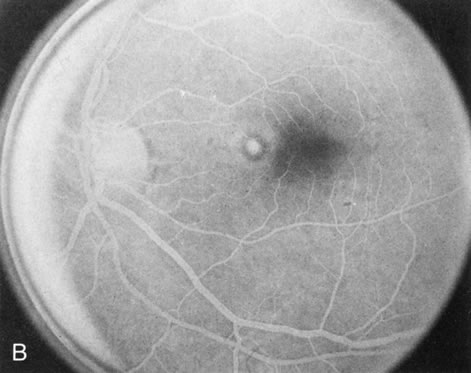

In Stargardt's disease, thes most common hereditary macular dystrophy, FA has a variety of functions. In the mildest fundus presentation, with visual symptoms and visual function out of proportion to the observed maculopathy, FA can confirm or even make the diagnosis and can avoid a mistaken diagnosis of malingering, hysteria, or central nervous system disease (Fig. 9A and B). When a maculopathy is present without surrounding parafoval flecks, FA may show patchy areas of transmission hyperfluorescence in the posterior pole, indicating a more diffuse involvement (Fig. 9C and D).

Fig. 9. Stargardt's disease–fundus flavimaculatus. The mild maculopathy (without parafoveal flecks) (A) is confirmed by the angiogram (B). The relative absence of the underlying choroidal flush, resulting in an easier visualization of the overlying retinal capillary circulation, has been referred to as the “silent” or “dark” choroid, and is considered a common finding in this disease. The diagnosis is confirmed in an individual with a pigmentary maculopathy without flecks (C). Here the angiogram demonstrates widespread transmission hyperfluorescence and a “silent” or “dark” peripapillary area (D). When the posterior pole shows multiple yellowish-white flecks (E), the angiographic findings do not necessarily correspond to the flecks (F). It should also be noted that despite the widespread abnormalities, the background choroidal fluorescence is normal.

In a large majority of patients (86% in one study),20 there is an absence or decrease in the background choroidal fluorescence (which is referred to as the “silent” or “dark” choroid) (see Fig. 9B). This warrants special attention because it occurs so frequently, is rarely found in other retinal disorders,21 and may be related to histopathology that shows an increase in lipofuscin in the RPE.22